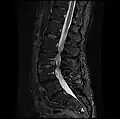

MRI lumbar spine with degeneration, post-hemilaminectomy L4-5 (sagittal T2 FRFSE)